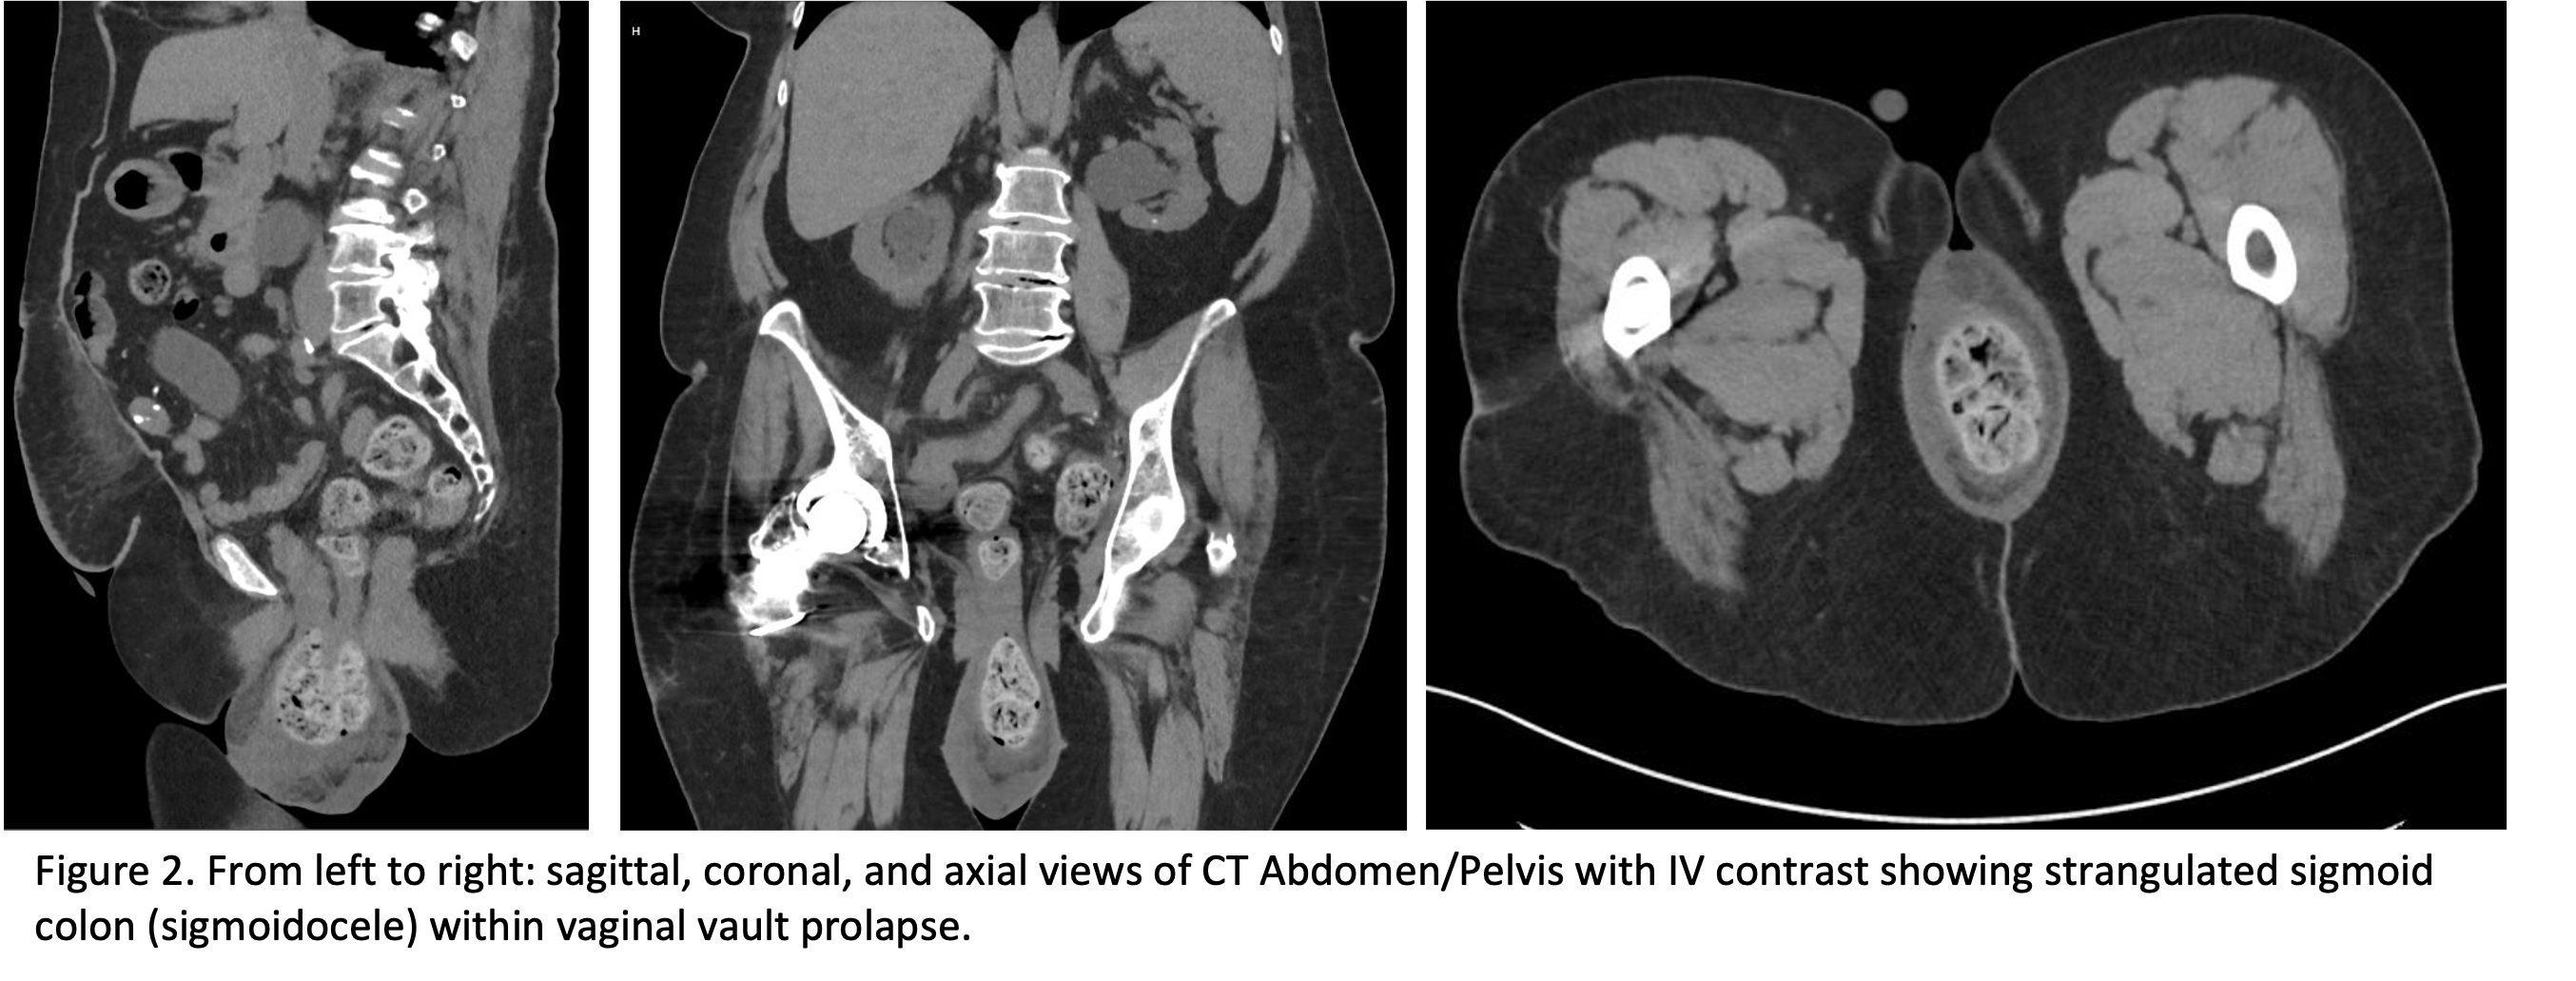

From Left to Right: sagittal, coronal, and axial views of CT Abdomen/Pelvis with IV contrast showing strangulated sigmoid colon (sigmoidocele) within vaginal vault prolapse.